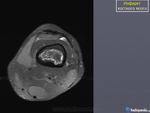

Женщина 1952 г.р.,направлена с диагнозом остеоартроз

Энхондрома, инфаркт кости, хондросаркома. Я в заключении такой бы диф. ряд написал.

На мой взгляд имеет место быть "Хрящевая матрица"

+1.Энхондорма? Хондросаркома?? Для уточнения рекомендована КТ коленного сустава.

Большое спасибо за комментарии!Сегодня пациентка принесла архивные снимки обоих коленных суставов,за 2008,2009,2011 года -картина такая же и на тех снимках,а на снимках правого коленного сустава за 2008 год такой же участок(немного меньших размеров) в области метадиафиза большеберцовой кости.Ни МРТ ни КТ никогда не делала.

Энхондрома все же не исключается.

Инфаркт костного мозга.

На представленных рентгенограммах паттерн действительного не "инфарктный", но спорить можно долго, а правду узнаем только выполнив МРТ или РКТ.

Возможности КТ и МРТ в диагностике данного дифряда широко известны и как безвредный метод исследования можно рекомендовать МРТ нижней трети бедра.